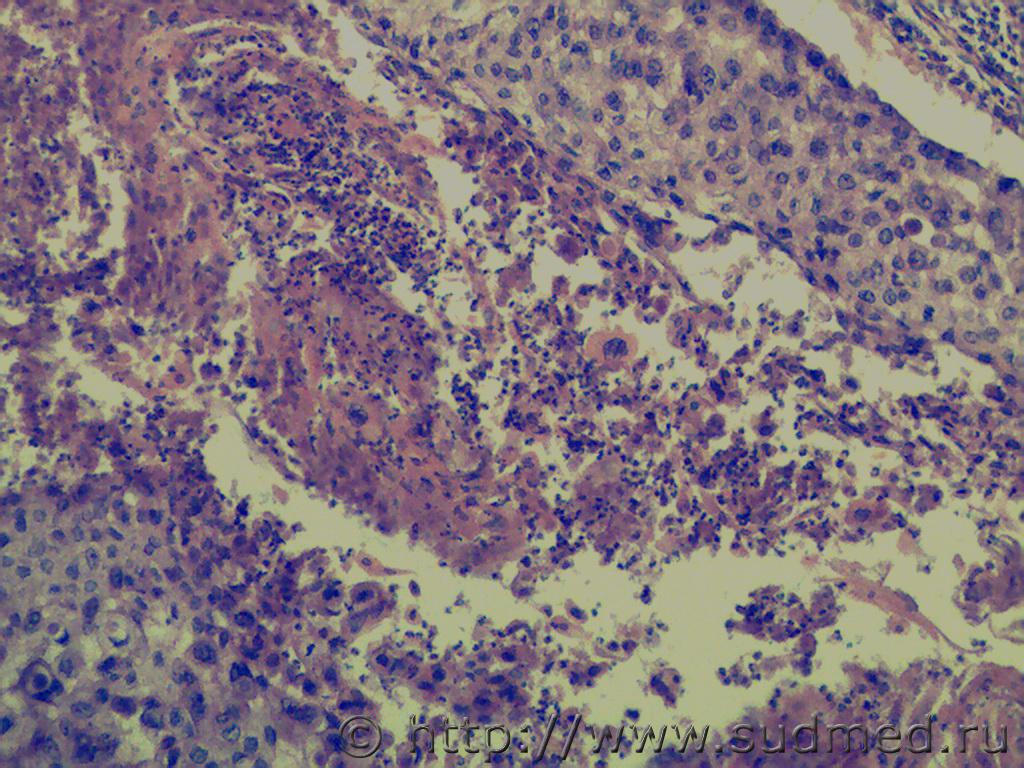

Плоскоклеточный рак ?

Мысль была,но здесь клеточный полиморфизм,патологическая митотическая активность,инвазивный рост.

Уважаемые коллеги, мое мнение - плоскоклеточный, G1-2, п/митозы есть, признаки инвазии, также согласен насчет инфильтрации как признака реакции.

Плоскоклеточный рак, т.к. есть жемчужины.

Если присмотреться внимательно, можно рассмотреть следующие патологические митозы:

1.К-митоз.

2.Рассеивание хромосом.

3.Паукообразный митоз.

4.Комковидный митоз.

5.Полая метафаза и т.д.

Добрый день, ув.коллеги! В данном случае нарушение базального слоя не видно, имеет место гиперплазия шиповатых клеток с полиморфизмом и митотической активностью ядер. Видны очаги кератинизации и кератиновых кист. На поверхности видны очаги изъязвления с клеточными детритами.

Нужно учитывать возраст и макроописание образования. Мое мнение указывает на себорейный кератоз с тенденцией к озлакачествлению. Нужно провести ИГХ.